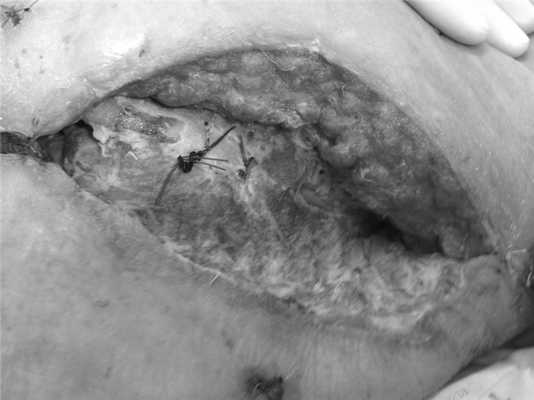

В результате проводимого лечения на 23-и сутки в локальном статусе раны отмечена выраженная положительная динамика в виде появления сочных грануляций и отсутствия фибринозных наложений (рис. 3). Рисунок 3. Внешний вид послеоперационной раны на 23-и сутки после экстренной операции. Остеомиелит и перихондрит ребер, разрастания сочных грануляций на стенках раны. Положительная динамика наблюдалась и в общем состоянии больной.